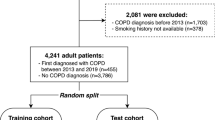

The PanCan study was a single arm lung cancer screening study which recruited from September, 2008, to December, 2010, in 8 Canadian centers. The study was approved at McMaster University by the Hamilton Integrated Research Ethics Board (project 08–367) and by the local ethics board at each study site. Candidates were screened for eligibility using the PanCan model, a prototype of the PLCOm2012 model, which included age (50–75 required), sex, smoking history, family history of lung cancer, personal history of chronic obstructive pulmonary disease, chest X-ray within 3 years, education level, and body-mass index, with the requirement for a 6-year risk of lung cancer ≥2% [24, 25]. Candidates were excluded for significant pre-existing cardiopulmonary conditions, prior lung cancer, other recent cancers, smoking cessation for greater than 15 years, pregnancy, or CT scan within 2 years. Consenting and eligible subjects undertook a detailed health and high-risk occupational exposure questionnaire (listed in Additional file 1: e-Appendix 1), spirometry, and LDCT of the chest. The study included autofluorescence bronchoscopy and blood biomarkers, which are not evaluated here [26]. The study achieved a 6.5% cancer incidence over a median 5.5 years of follow-up [24].

Among 2537 subjects recruited to the PanCan study, 2514 had available spirometry data and were included in the analysis. Of these, 527 self-reported a prior diagnosis of COPD and 1987 did not (Table 1). Those reporting a prior diagnosis of COPD were more likely to be female (52 vs 42.7%), were less likely to have completed a secondary school education (14.5 vs 22.2%) or completed post-secondary education (41.6 vs 48.6%), and had a higher mean pack-year smoking history (52.5 vs. 50 years) (all p < 0.001). A reported prior COPD diagnosis also conferred a higher likelihood of reporting symptoms of dyspnea, cough, phlegm, or wheeze, a greater likelihood of having one or more chest X-rays in the last 3 years (77 vs 54.9%), and a more common history of other respiratory disease (asthma, pneumonia, respiratory failure) (all p < 0.001).